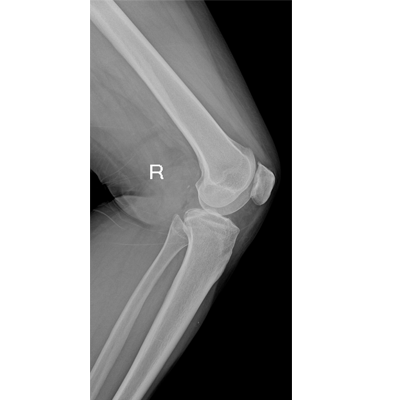

● 數(shù)字化無線平板成像,操作簡便,成像質(zhì)量高